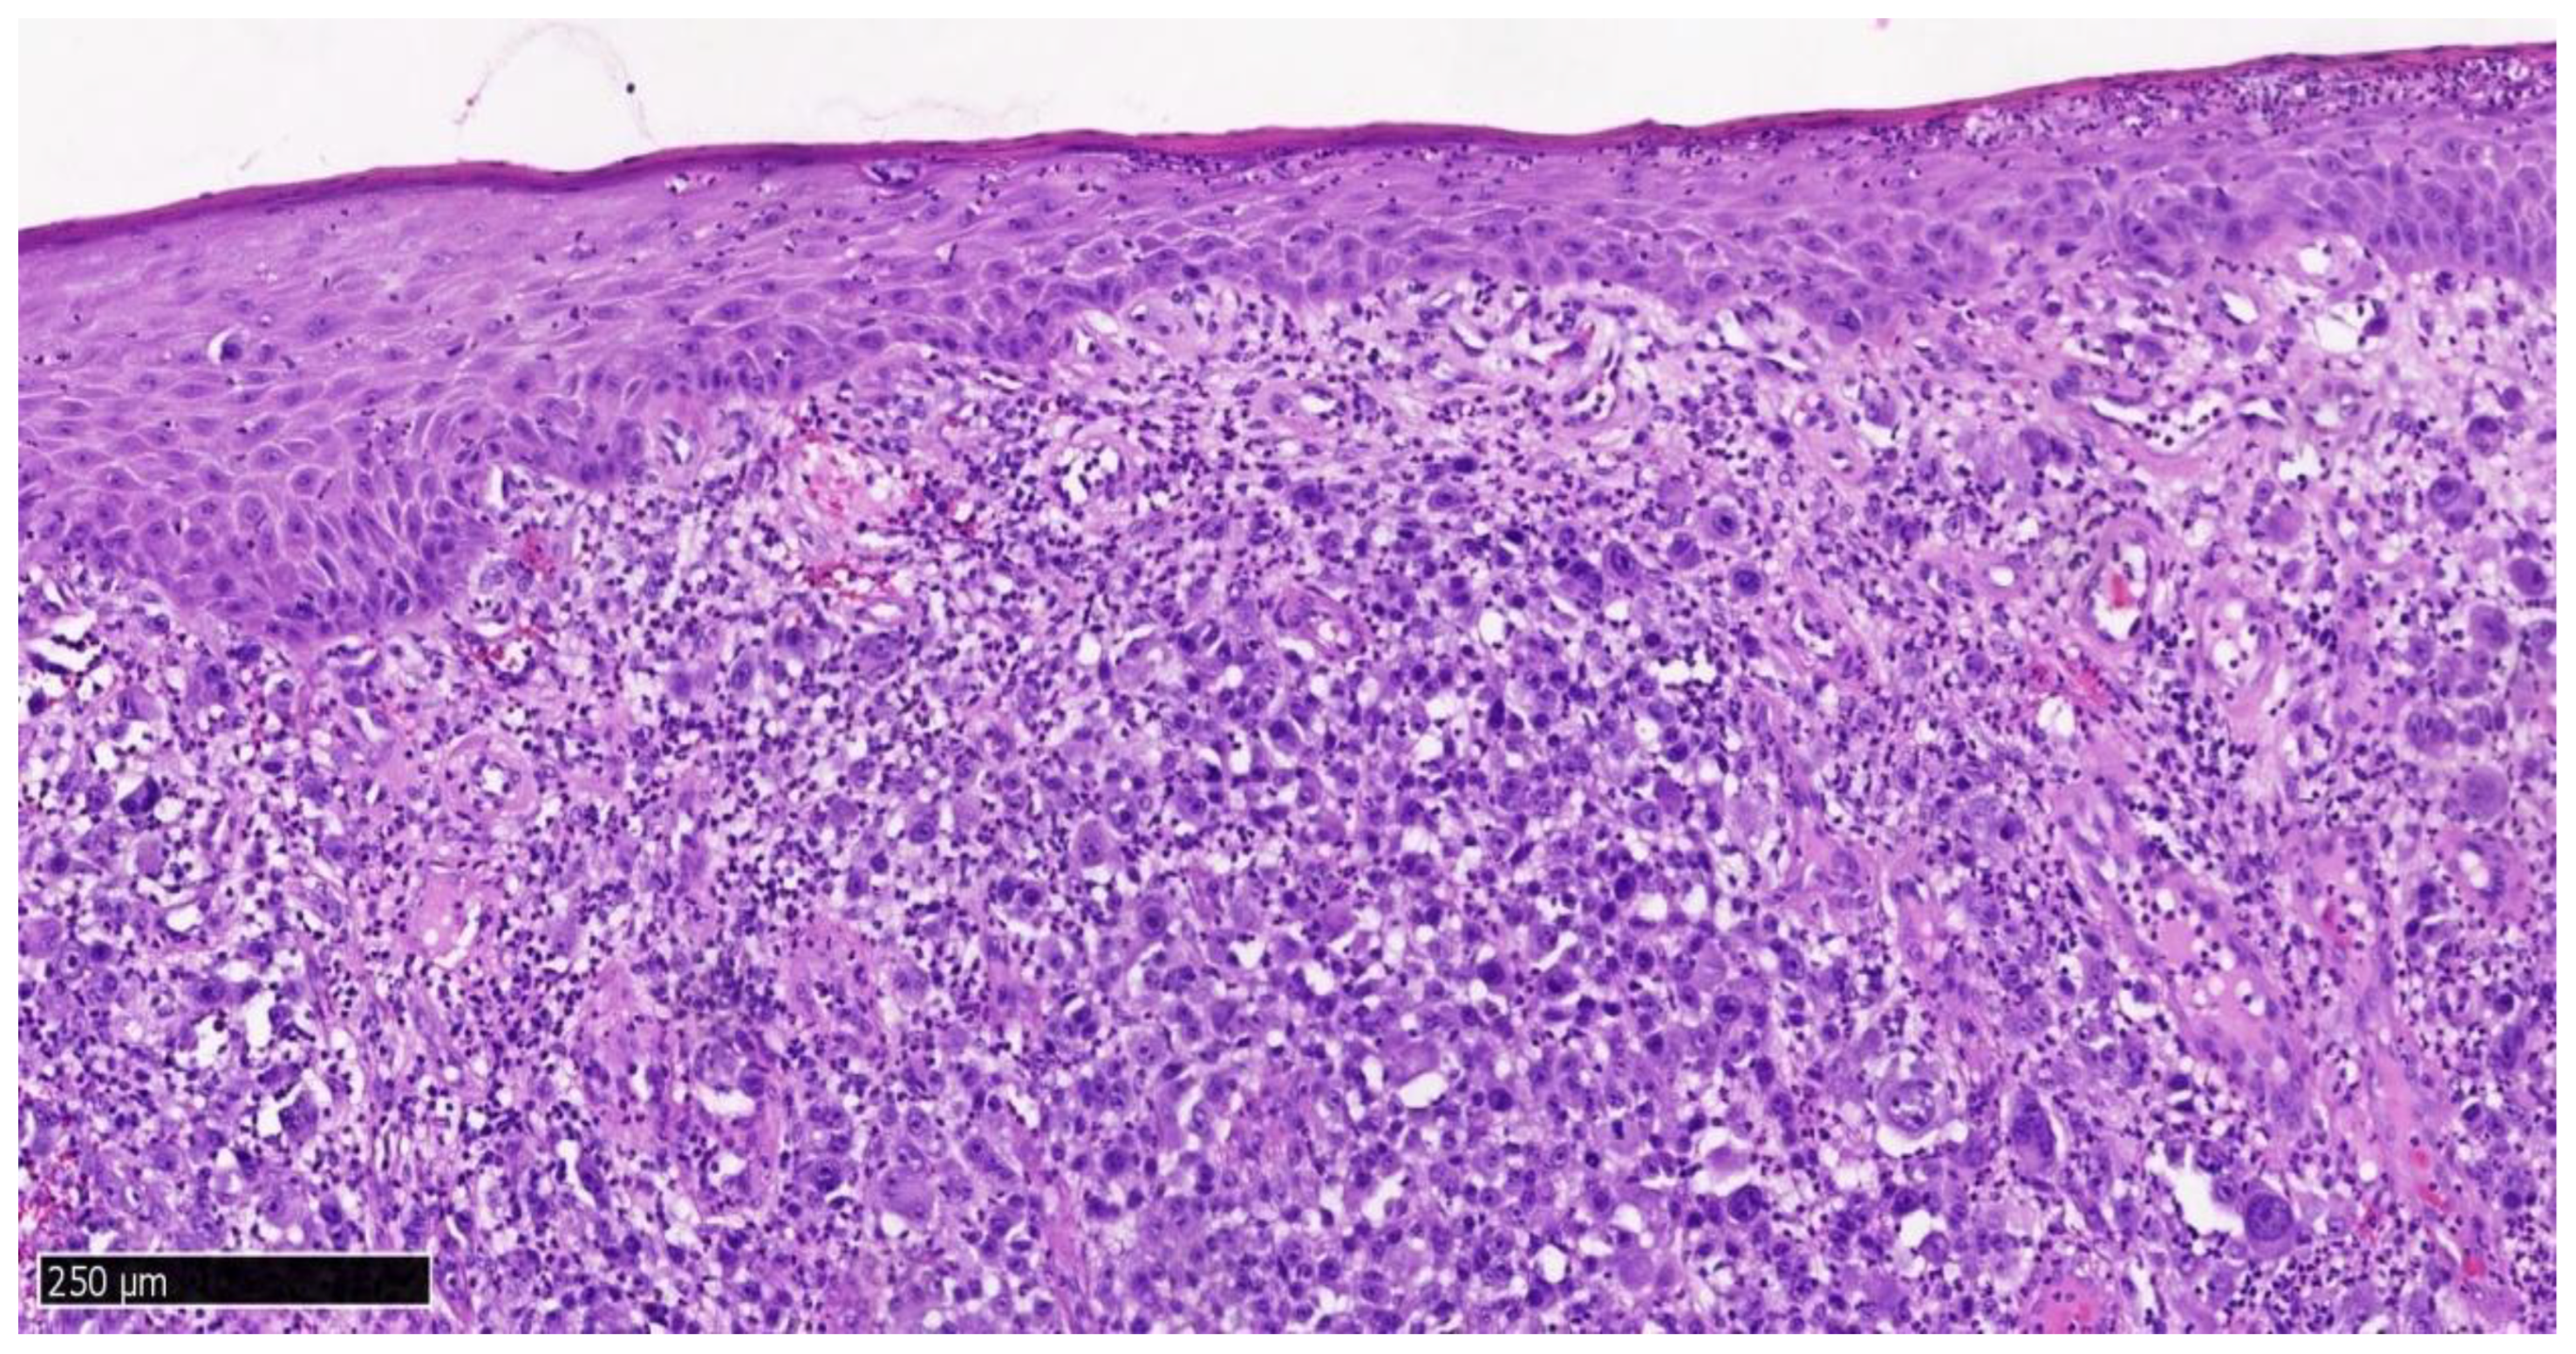

Maxillary lesion: infiltrating melanoma, mitotic index 14/mm2, ulceration present, margins involved (Figure 4, Figure 5 and Figure 6).

Histologically, amelanotic oral mucosal melanoma consists of spindle cells with numerous mitotic figures and no cytoplasmic melanin pigmentation. These malignant tumor cells are characterized by significant pleomorphism, with large, irregular, hyperchromatic nuclei and prominent nucleoli [18]. The cells of malignant oral mucosal melanoma can be visualized using hematoxylin and eosin staining. However, if melanin is absent in amelanotic melanoma, immunohistochemical (IHC) staining should be performed to obtain additional diagnostic information. CK and LCA staining are used for differential diagnosis with squamous cell carcinoma and lymphoma. The IHC panel in our case (SOX10/S100 positive; CK Pan negative; variable melanocytic marker expression) aligns with recommended diagnostic strategies for OMM. Specifically, SOX10 has demonstrated greater expression stability compared to S100 in melanoma diagnostics, while Melan-A may be negative in amelanotic variants, highlighting the need for panel-based interpretation rather than reliance on individual markers [17,32]. Moreover, a very high Ki-67 index (70–80% in our case) and elevated mitotic index (MI: upper gum tumor—14/mm2; lower tumor—5/mm2) correspond with more aggressive tumor biology and poorer prognosis in head and neck OMM. High Ki-67 proliferation indices (60–100%) have been correlated with shorter overall survival in mucosal melanoma patients [33,34].

Figure 4. Hematoxylin and eosin staining, final magnification ×100, specimen from the upper gingival tumor. Scale bar: 250 μm.